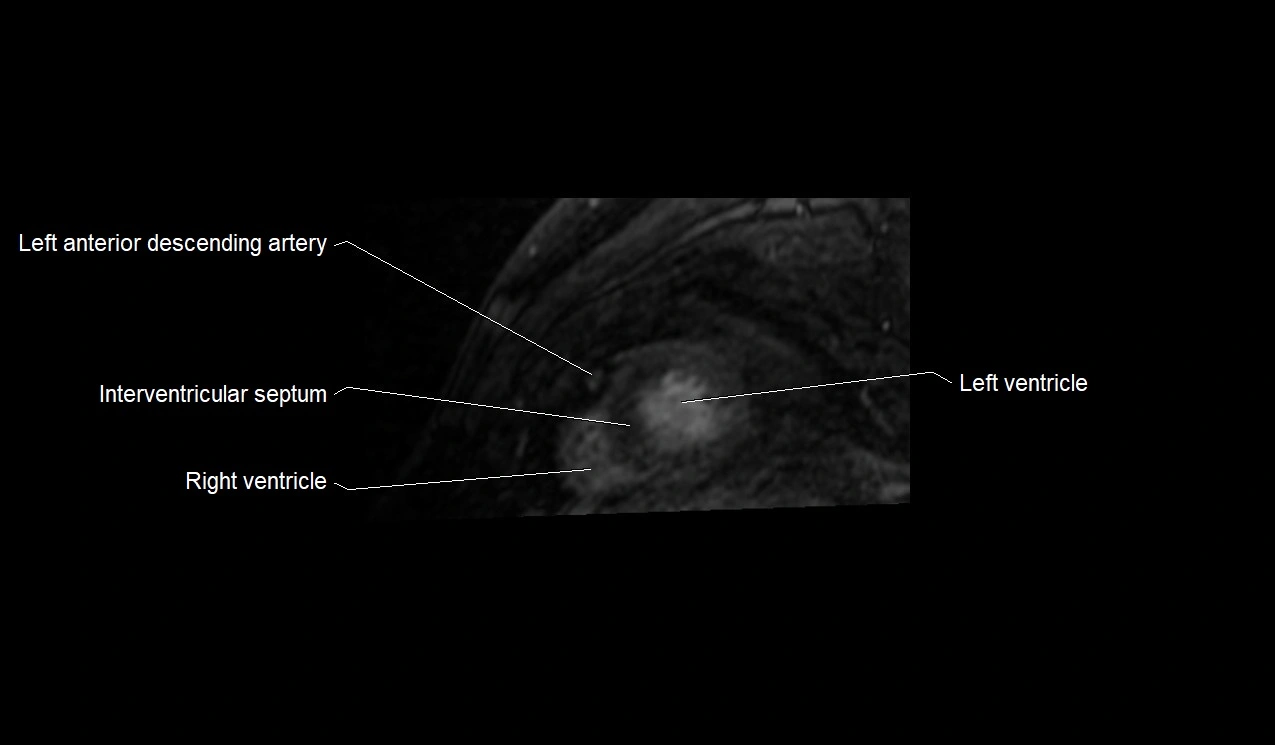

MRI image